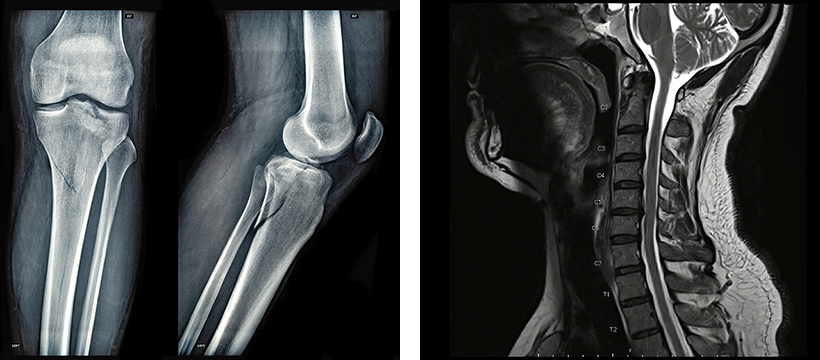

頚椎症性脊髄症の症例

脊髄 50代男性

歩行距離が300mから5kmに回復

治療前

300m

治療後

5km

頚椎症性脊髄症の術後も症状が残存。脊髄腔内に2,500万個を3回投与。歩行距離が約17倍に改善し、膀胱直腸障害も改善。

MRI画像検査予約

2

必要に応じてMRI検査を予約。現在の状態を正確に把握します。